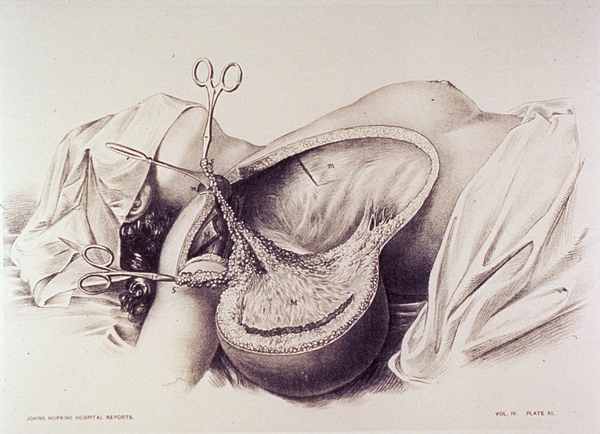

1855年5月3日

第一例子宫切除术被报道。患者是一名34岁的子宫肌瘤患者,在每次月经来临时都会有致命性的出血。作者称子宫切除手术是"最后的办法"(a last resort)。